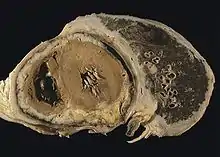

![]() | |

CT scan showing a left sided mesothelioma with an enlarged mediastinal lymph node | |